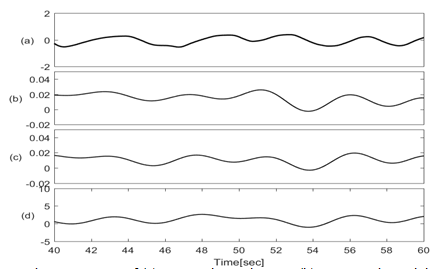

Figures 3 & 4 show the baseline wondering and amplitude modulation of SCG signals plotted along with lung volume changes that are calculated from respiratory flow measurements.

Figure 3 Traces of (a) Lung volume changes; (b) SCG-craniocaudal baseline; (c) SCG-lateral baseline; (d) SCG-dorsoventral baseline signals.